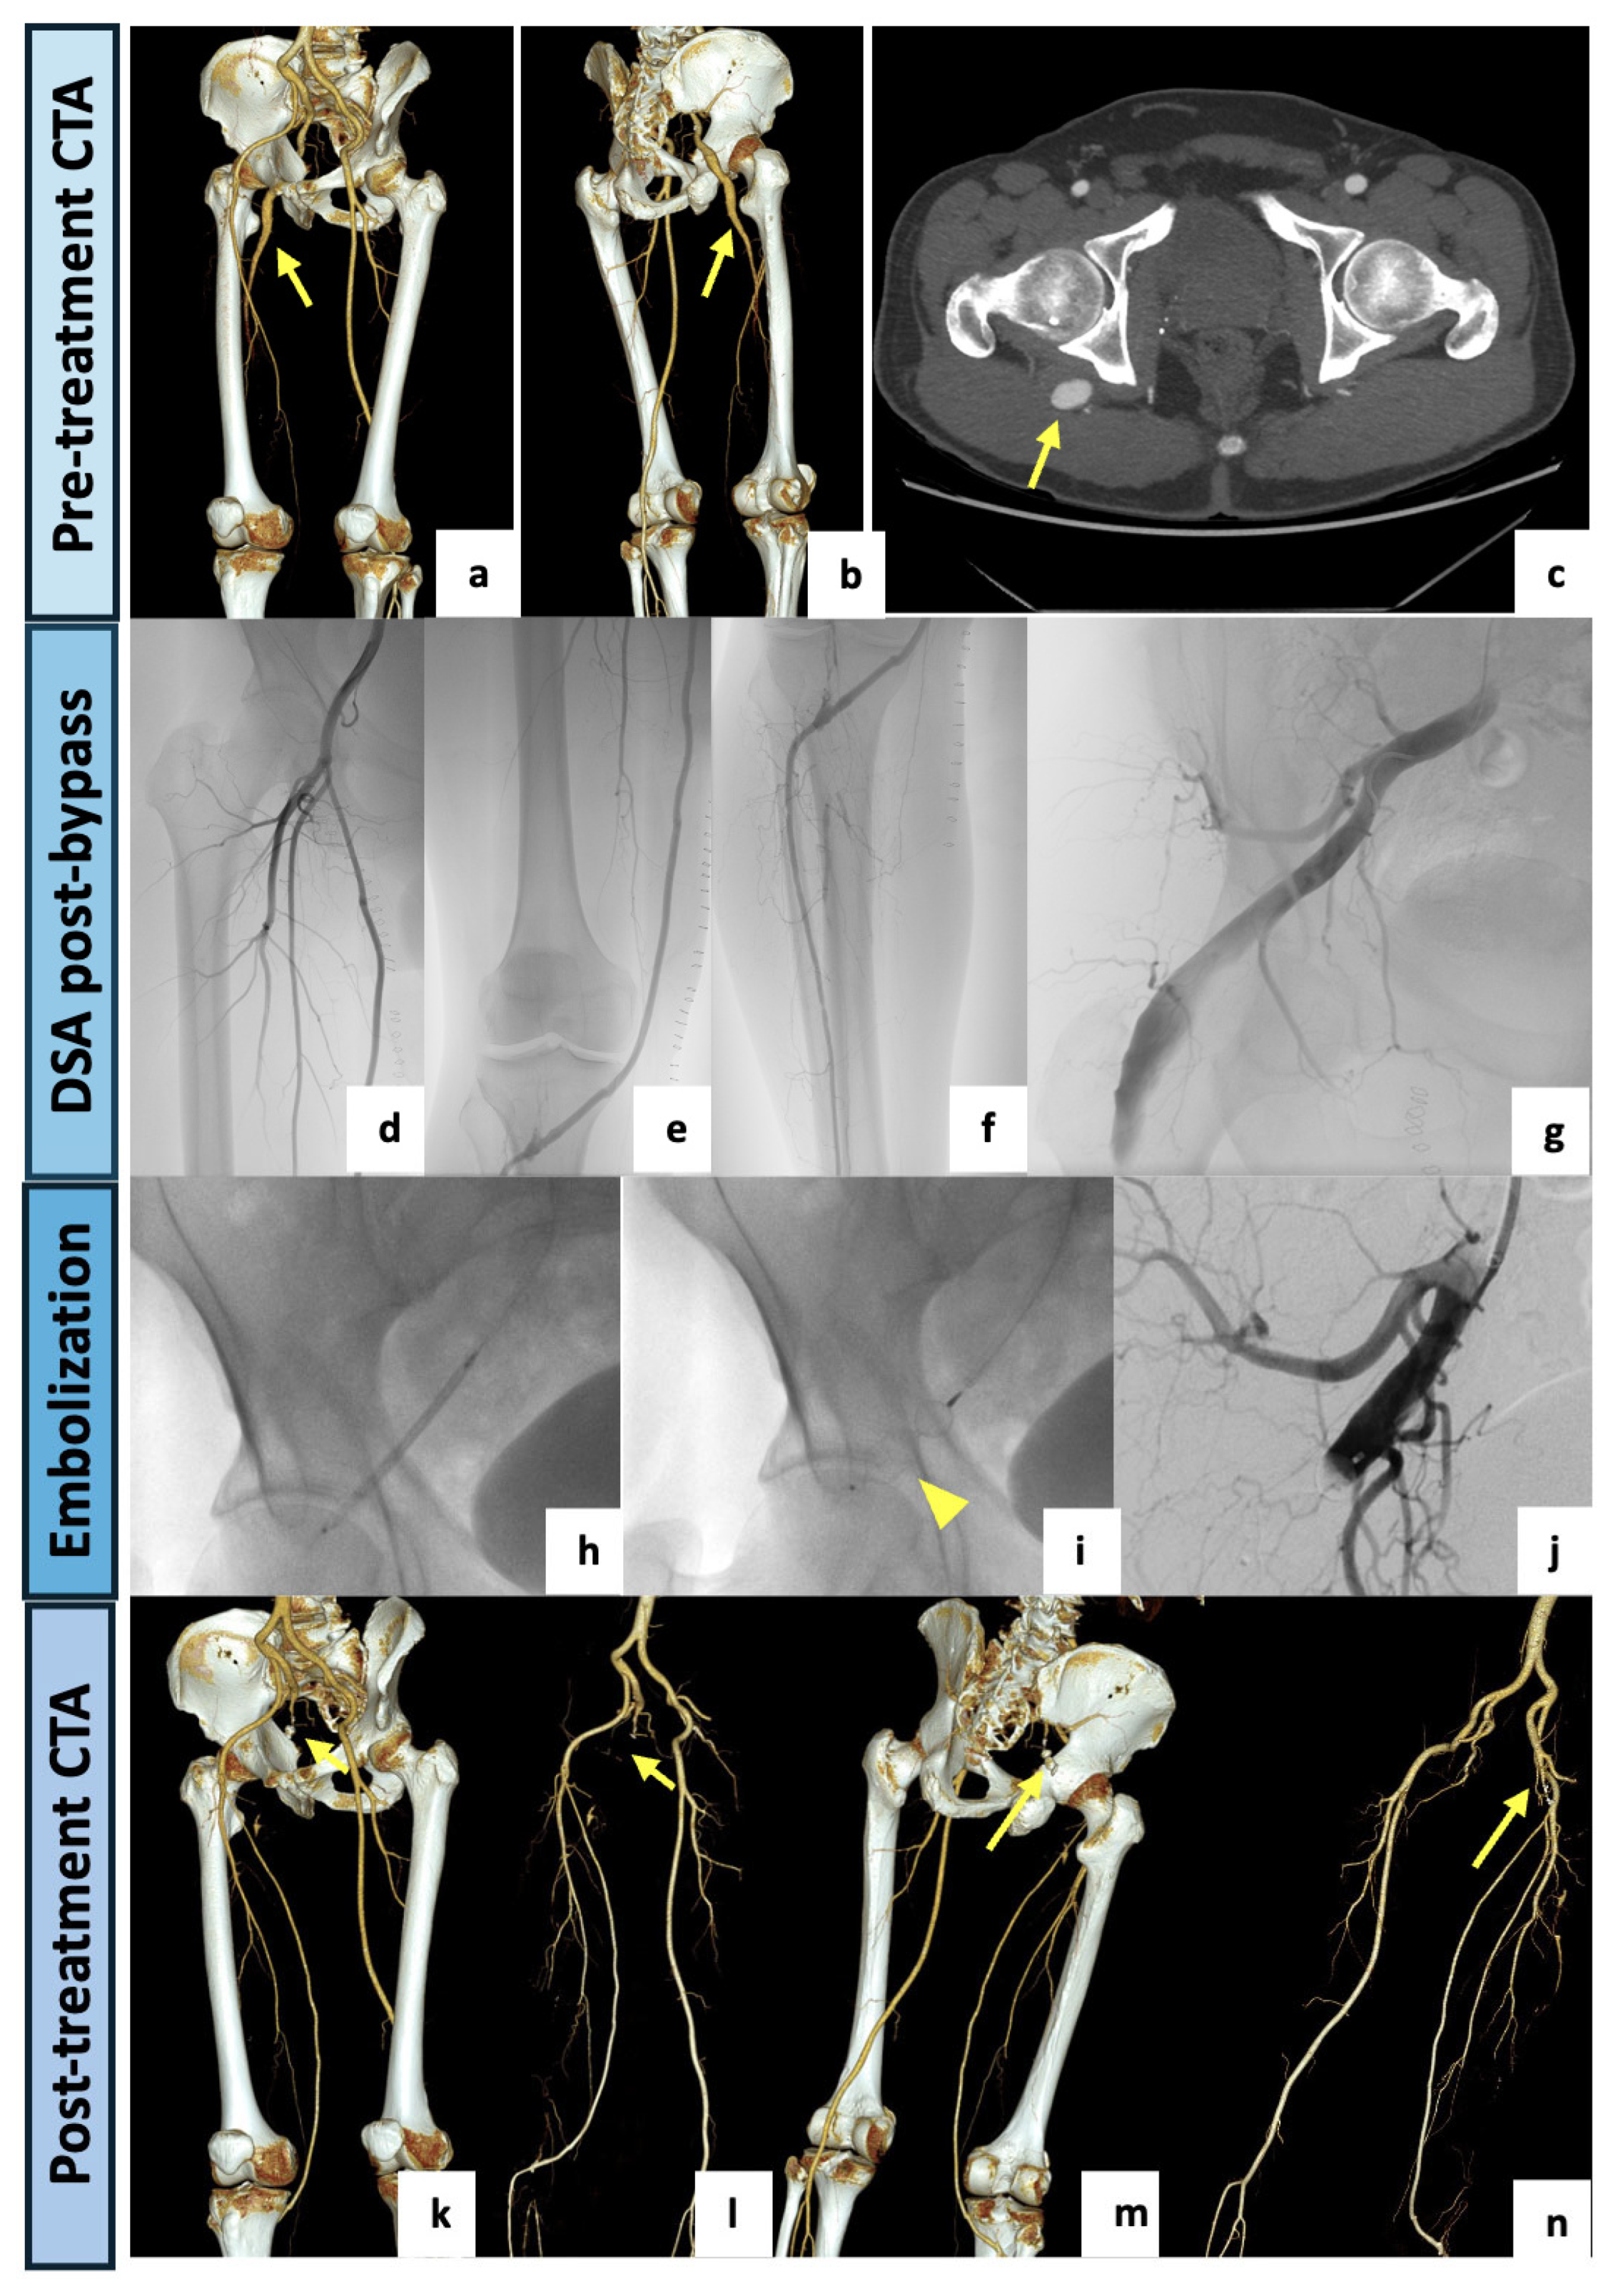

Figure 3.

(a,b) VR reconstruction of the preoperative CTA showing a right complete PSA originating from the internal iliac artery (arrow). The right external iliac artery appears hypoplasic and the SFA appears incomplete and diminished in caliber (type 2a). (c) Axial view showing an aneurysmal dilatation (23 mm) of the PSA with luminal thrombus (arrow). A hybrid approach was preferred, with the first step consisting of a left femoro-tibial bypass with the anterior tibial as the target artery. (d–f) Selective angiographic images preliminary to the endovascular step showing a patent femoro-tibial bypass. (g–j) After a contralateral 6F-sheat femoral access, the aneurysmal PSA was selectively catheterized and completely embolized using a 12 mm Amplatzer Vascular Plug II (arrowhead) deployed immediately distally to the internal pudendal artery origin. (k–n) VR reconstructions of the postoperative CTA (3-month) demonstrating the patent femoro-tibial bypass with complete exclusion of the aneurysmal PSA (arrows).